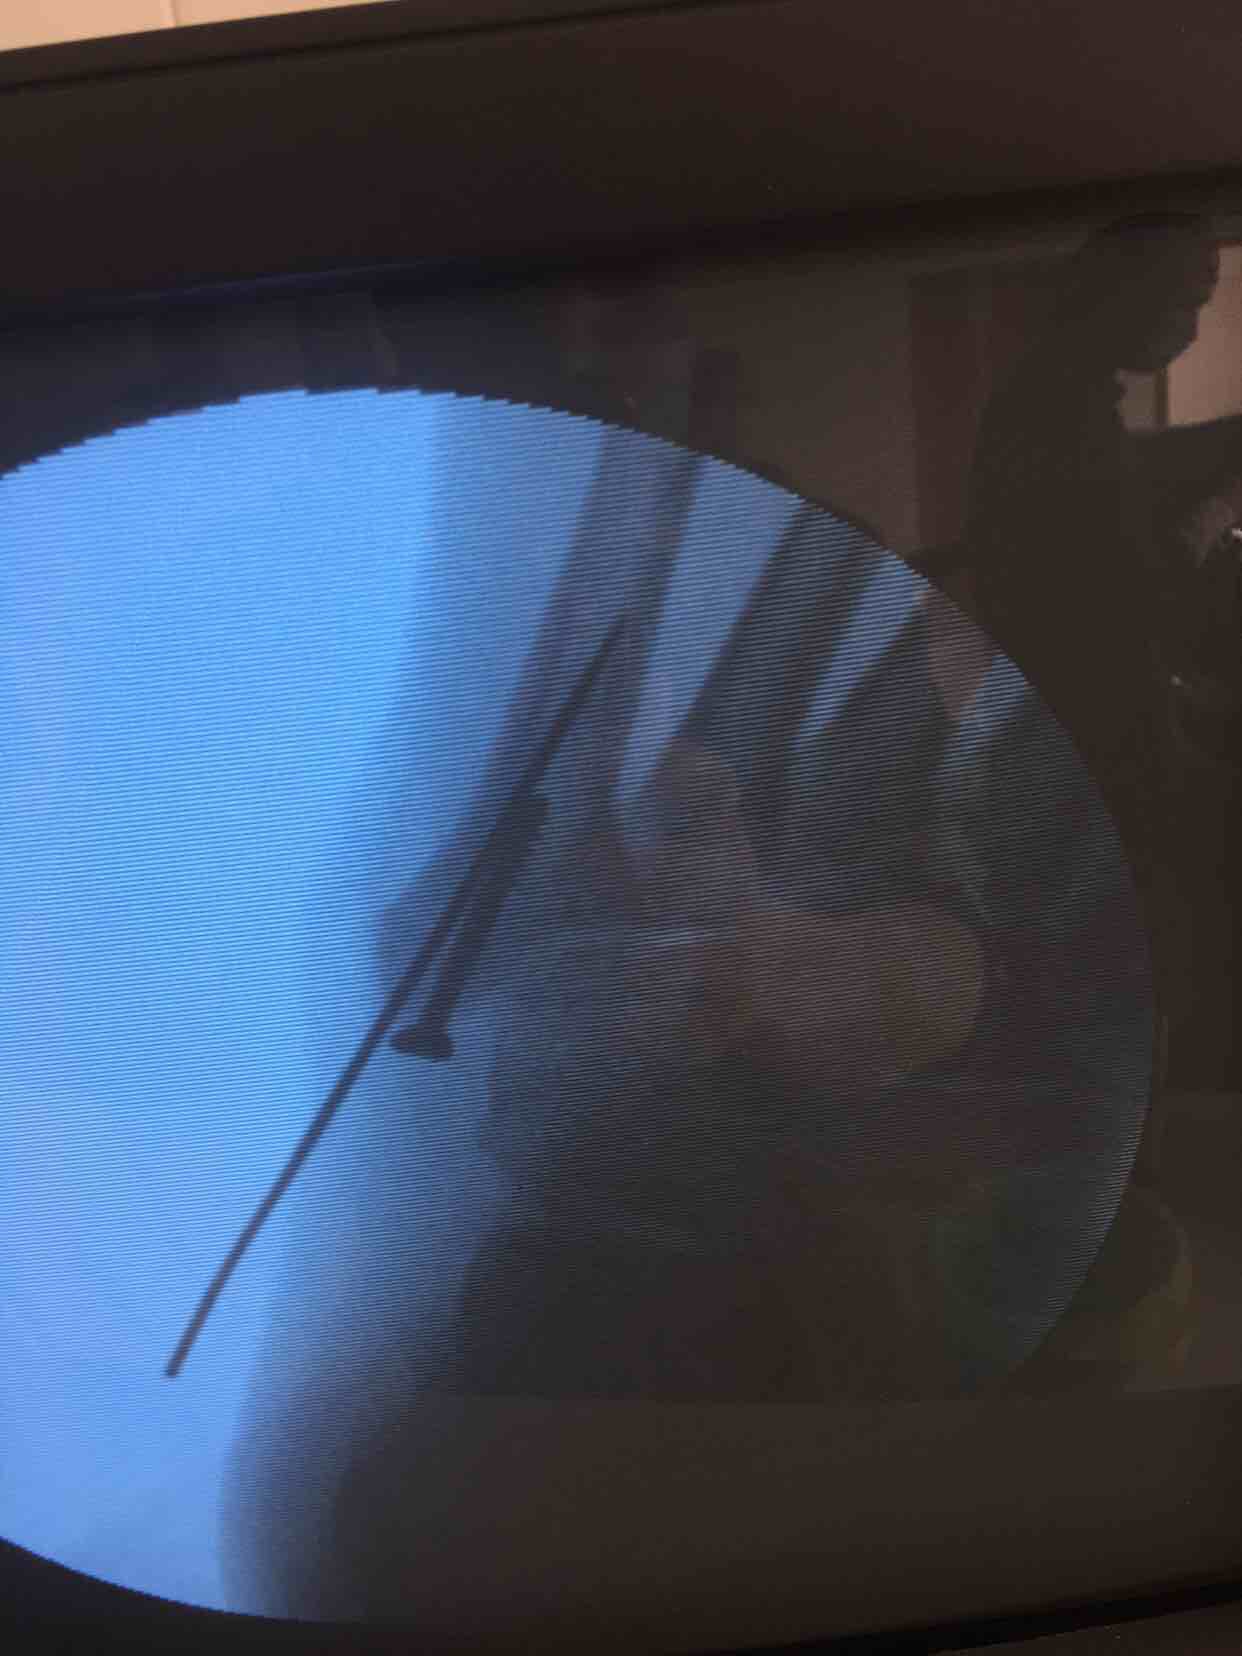

第五跖骨基底部骨折(切开复位内固定术)

摔伤后右足肿痛,活动受限16天入院。既往身体健康,无特殊不良嗜好。

心肺复未见异常,生命体征平稳。右足肿胀基本消退,局部皮色皮温基本正常,压痛及纵叩痛阳性,末梢血运感觉基本正常。

诊断第五跖骨基底部骨折(右)完善术前检查,在腰麻下行切复内固定术,术后抗炎,消肿等对症处理。